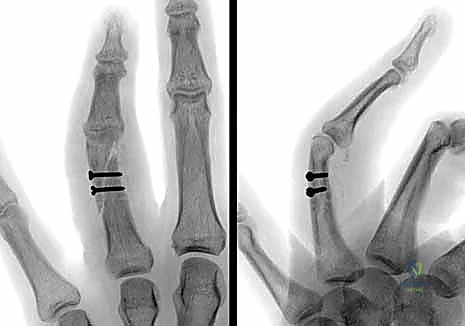

2. الرد المفتوح والتثبيت الداخلي (ORIF - Open Reduction and Internal Fixation):

في الكسور المفتتة أو المعقدة، يقوم الدكتور هطيف بعمل شق جراحي دقيق (غالباً من الجانب لتجنب الأوتار الظهرية) لكشف الكسر وإعادة ترتيب الشظايا العظمية بدقة متناهية، ثم تثبيتها باستخدام:

* البراغي الساحبة (Lag Screws): تُستخدم في الكسور المائلة الطويلة أو الحلزونية لتوفير ضغط قوي بين حواف الكسر.

* الصفائح والبراغي الدقيقة (Mini-plates and Screws): تُستخدم في الكسور العرضية أو المفتتة لتوفير تثبيت صلب وقوي يسمح بحركة الإصبع في اليوم التالي للعملية.